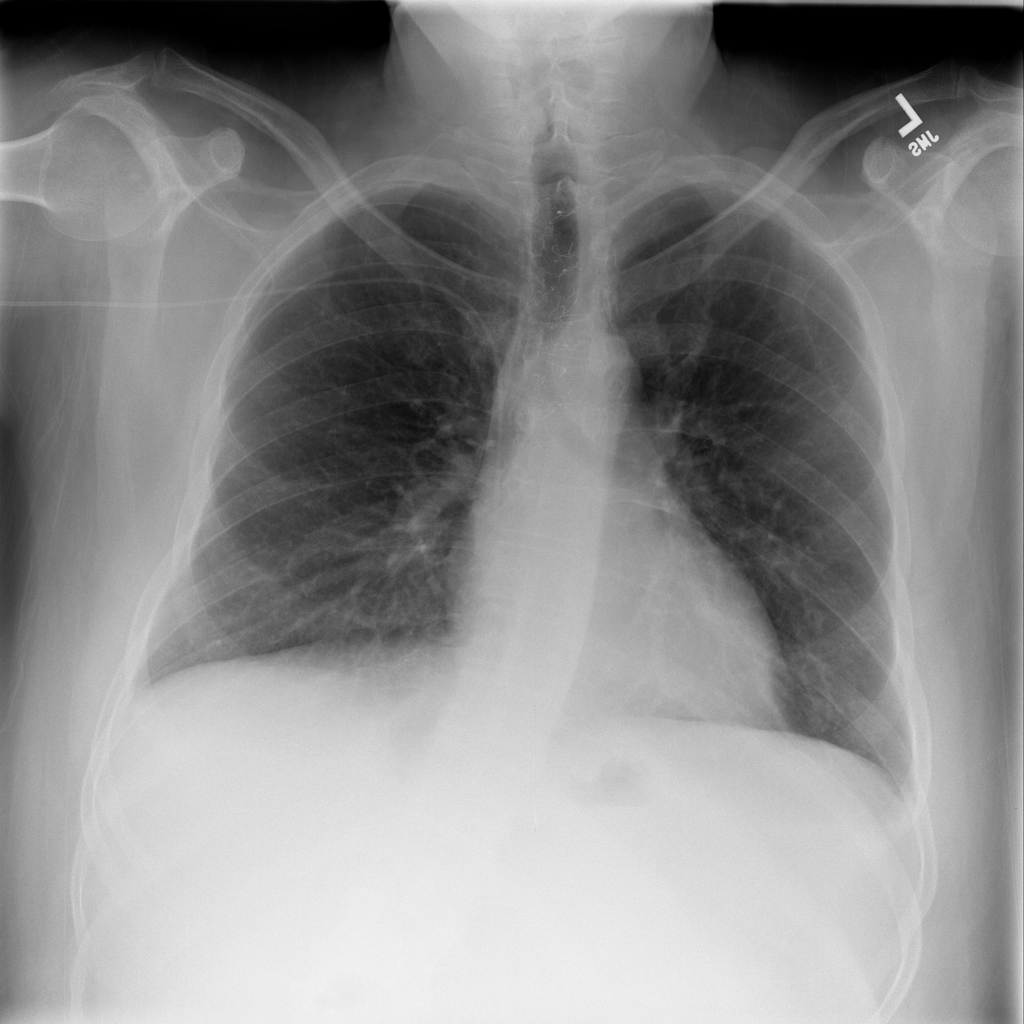

Pleural Effusion

Pleural effusion means extra fluid has collected around the lung in the pleural space. It can happen with heart problems, infection, inflammation, or other underlying conditions.

Showing up to 90 reference images for Effusion.

PAT-E81B · IMG-000Effusion

PAT-E81B · IMG-000

PA